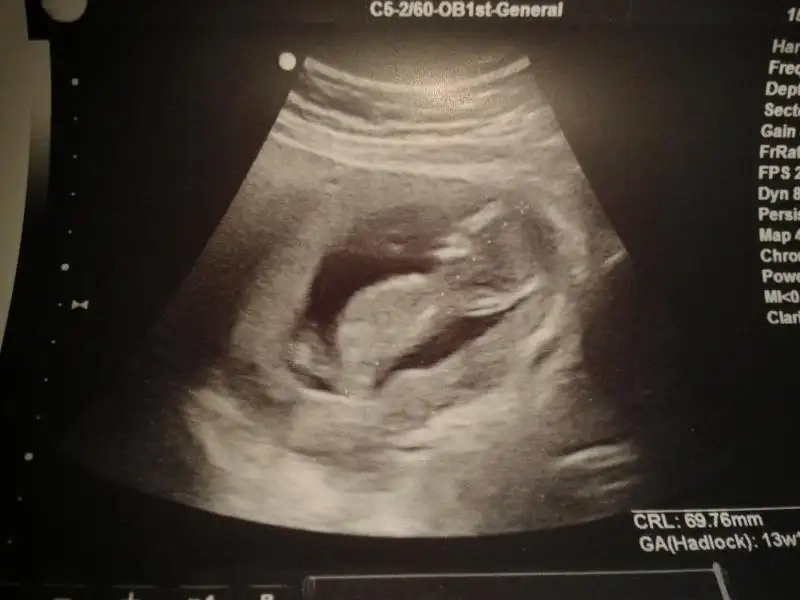

dr soylemeden siz gorun genital nub teorisi ( bebegin cinsiyeti)

çok ilginç bi yöntem...bunu bütün doktorların biliyor olması gerekmez mi??bizimki 16. haftadan önce kesinlikle söylemiyor

15+3 te gittim doktora cinsiyetini öğrenmek için.ramazanın son günü diye niyetlenmiştim.hadi bismillah ya arif ya arife gelecek dedim yok bebek kıpırdamıyordu.pozisyonu da iyi değildi.doktor bi ton kızdı...'aç ayı oynar mı' dedi bide yaaaaaa

'erkeğe benziyor kordon değilse kimseye söylemeyin' dedi gönderdi bizi